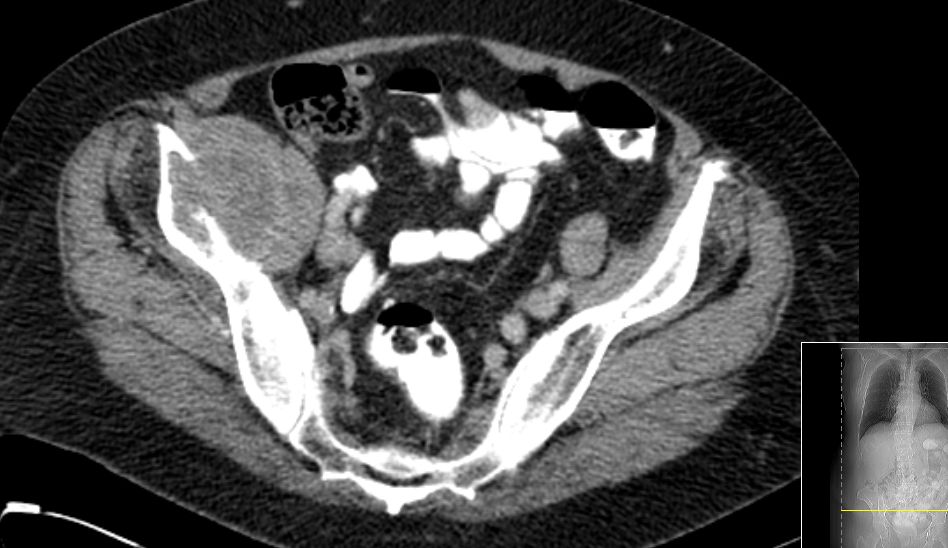

| Fall | 75-jährige Frau mit zunehmenden Schmerzen der rechen Leiste

und Hüfte seit 3 Monaten. ![]() |

CT: 6,4 x 4 cm große kapsulierte tumoröse Raumforderung in der Fossa iliaca rechts mit knöchernen Destruktion des Os

ileum. Dichte bis 20 HEs.![]() |